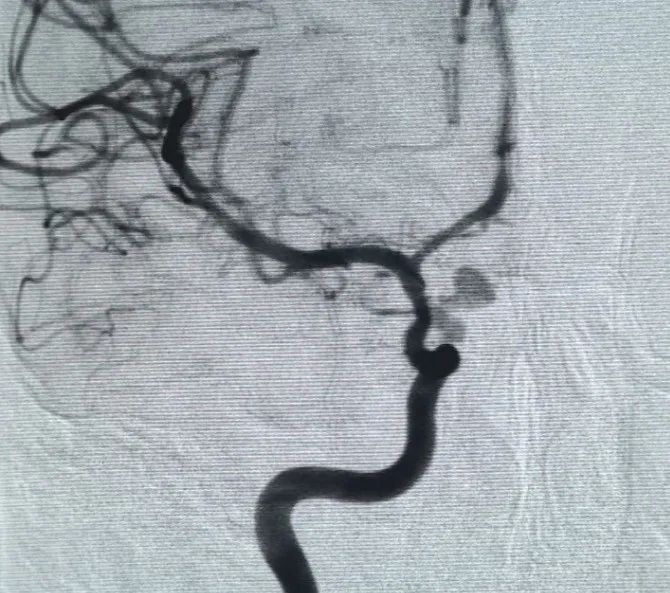

Перфиллер®Расширяемая катушка 3 мм × 6 см и перфиллер®Затем была помещена расширяемая катушка 3 мм × 2 см, чтобы завершить окклюзию шеи. Впоследствии, Нува®Отвод потока (TJED-D-5.0-16) был доставлен и развернут через шейку аневризмы. Последующая ангиография как на передне-задних, так и на боковых видах подтвердила отличное покрытие, хорошее расположение стенок и четкую рентгеноконтрастность с заметной контрастной стагнацией.

Процедура была завершена гладко, без осложнений, и пациент выздоровел без неврологических дефицитов.